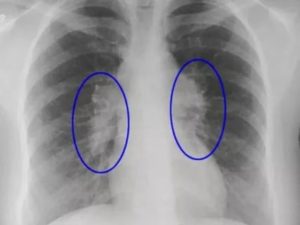

Для визуализации патологического процесса назначается рентгенологическое исследование органов грудной клетки, которое позволяет обнаружить изменения в легких. Обнаруживаются изменения с обеих сторон, преимущественно в нижних отделах легких.

Отмечаются усиление и деформация легочного рисунка, постепенно формируется картина так называемого «сотового легкого», которое характеризуется образованием кольцевых теней диаметром 3 – 7 мм со стенками толщиной до 3 мм, что в некоторой мере напоминает пчелиные соты.